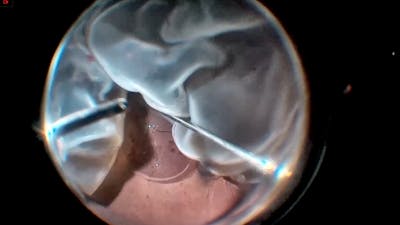

The RETINAWS panel led by Kourous Rezaei, MD, discuss techniques for vitreoretinal surgery and rare surgical cases.